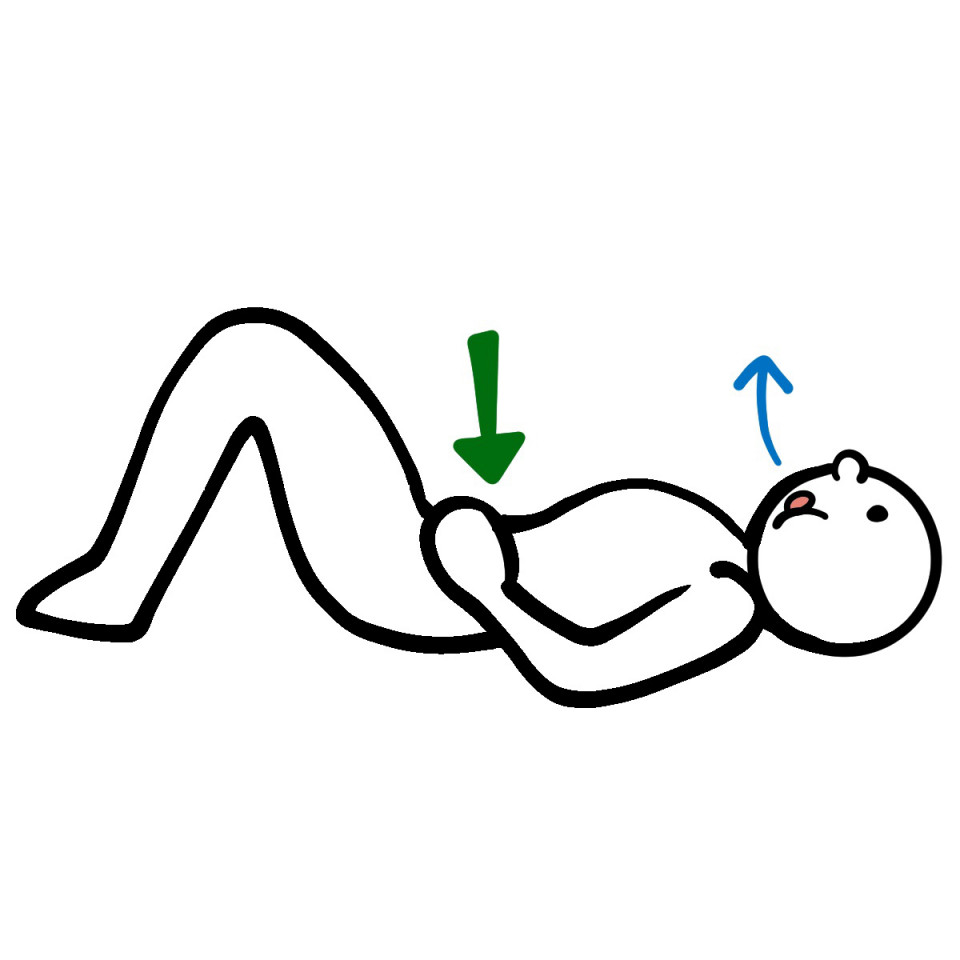

3腹圧をあげてインナーマッスルの活性化 (お腹を凹ませる意識で)

痛みが出る場合は無理に行わず優しくゆっくり時間をかけて行うか、原因が違うこともありますのでやらない方がいい場合もありますのでご自分の体に合わせて行ってください。